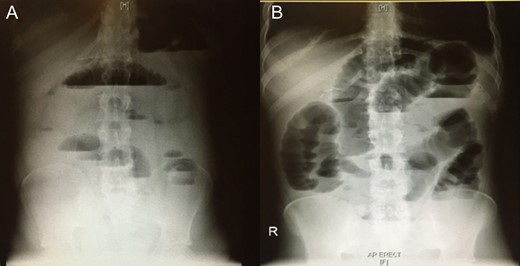

Blood was drawn for a complete blood count, urea and electrolytes, liver function test, coagulation profile, serum glucose level, carcinoembryonic antigen and cancer antigen, and the results were all within normal limits. An initial abdominal X-ray showed multiple air fluid levels and a dilated bowel (Fig. 1A and B). A computed tomography scan of the abdomen and pelvis showed small bowel obstruction to the level of the proximal ileal loops, with a transition point between the dilated proximal loops and the collapsed terminal ileal loops (Fig. 2A and B).

A computed tomography of the abdomen and pelvis showing small bowel obstruction at the level of the proximal ileal loops, with a transition point between dilated proximal loops and the collapsed terminal ileal loops.